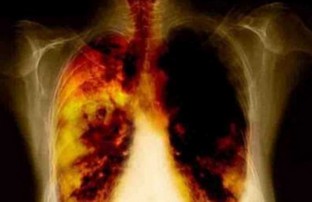

1. РАК ЛЁГКОГО. Курильщики составляют 96-100% всех больных этим жутким заболеванием. Вещества табачного дыма вызывают мутации гена р53, а половина всех злокачественных опухолей человека образуется из-за нарушений именно этого гена. Не случайно у курящих людей в 20 раз чаще возникают раковые опухоли нижней губы, языка, гортани, пищевода, желудка, почек и шейки матки.

2. ХРОНИЧЕСКИЙ БРОНХИТ. Курение препятствует самоочищению дыхательных путей и провоцирует развитие воспаления. Бронхит - это постоянный кашель плюс неприятный запах изо рта. Далее развивается эмфизема легких, при которой грудная клетка раздувается, как бочка, и жить становится совсем невмоготу